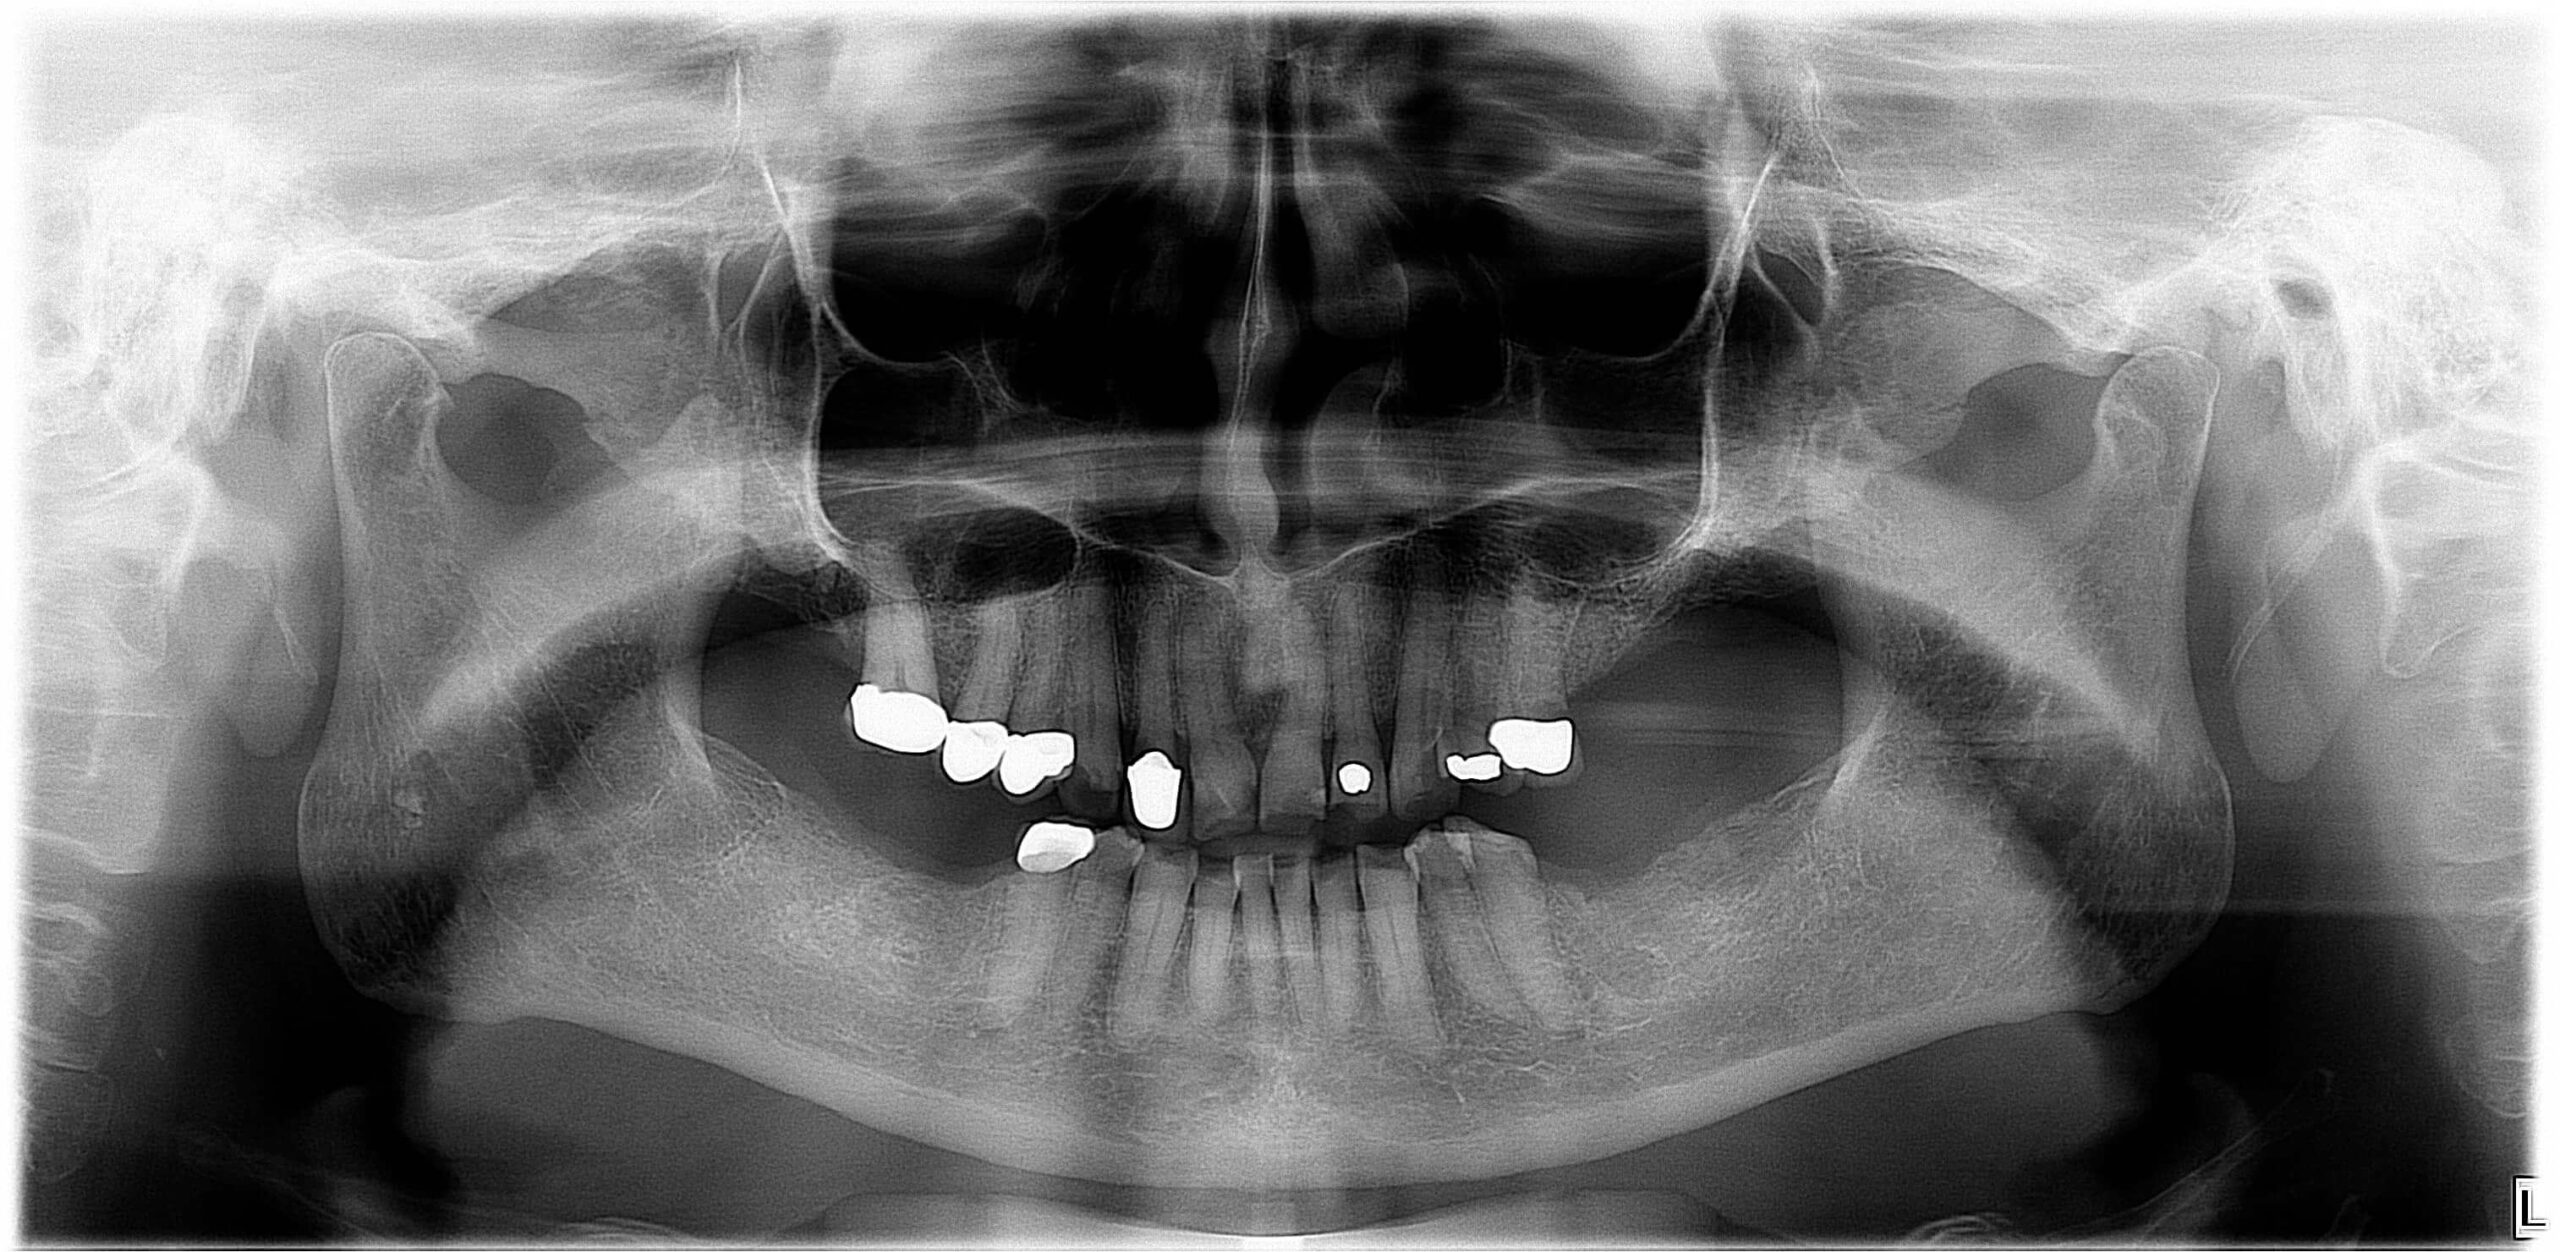

Páciensünk néhány éve már folyamatosan tapasztalt állkapocsízületi kattogást – ám nem tudta, hogy ez figyelmeztető jel, és amikor a szájnyitási korlátozottság is bekövetkezett, még akkor sem fordult azonnal orvoshoz. Az erősen beszűkült szájnyitás miatt nagymértékben megromlott a szájhigiéniája is. Fogait és régebben készült pótlásait nem tudta megfelelően tisztán tartani, így a szájüreg állapota rohamos romlásnak indult. Több fogát is el kellett távolítani, mert konzervatív eljárással már nem voltak kezelhetők. (1., 2. kép)

Páciensünk azért kereste fel fogászatunkat, mert jobb felső kismetszőjénél erős fájdalom jelentkezett. Kiderült, hogy a fájdalom oka egy komoly szuvasodás. A panaszokat okozó fogat és a bal[M1] felső kisőrlőt a nagyfokú szuvasodás miatt sajnos el kellett távolítanunk. (3. kép)